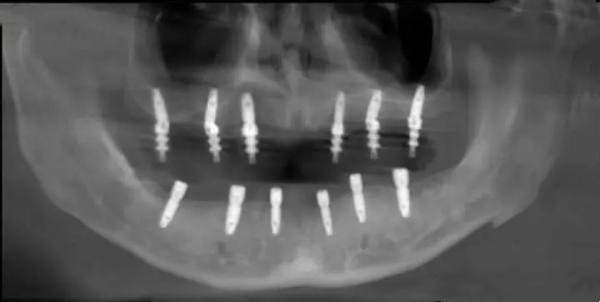

上海宝山正规种植牙医院及具体价格列表

以下是宝山本地口碑较好的民营口腔机构,价格透明且植体有资质,地址和电话均为真实可查:

上海宝山种植牙价格行情(按植体品牌/技术分类)

2025年宝山种植牙价格主要根据植体品牌和技术划分,具体如下: